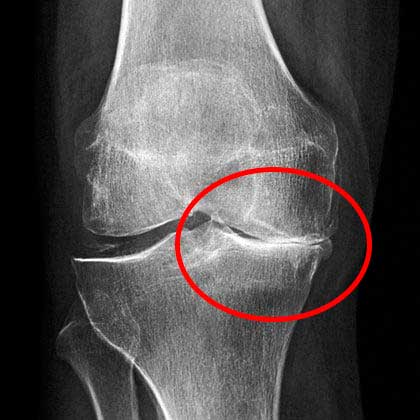

Kondisi lutut saya kala itu. Rasa sakit yang kuat

Di sana dokter melihat hasil rontgen cukup lama, kemudian menyampaikan bahwa saya tidak bisa melakukan pekerjaan fisik lagi dan mengangkat beban dengan berat lebih dari 2 kilo.

X-ray menunjukkan masalah serius dengan lutut saya

Berikut adalah kondisi lutut saya yang sehat saat ini